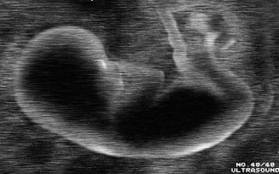

210. Η Αμφιβολία

Σε συζητήσεις (όλο και σπανιότερες, είναι η αλήθεια) για το τι μας περιμένει στο επέκεινα, συνήθως λέω: «Μετά τον θάνατό μου περιμένω ό,τι και πριν τη γέννησή μου: τίποτα». Δεν θυμάμαι αν η ατάκα είναι δική μου ή αν την έχω αλιεύσει από άλλον· δεν έχει μεγάλη σημασία: ας τη θεωρήσουμε «πνευματική χρησικτησία» για να πάμε παρακάτω. Έχω σκεφτεί ένα αντεπιχείρημα, το οποίο –αφού δεν έτυχε να μου το αντιτάξει κανείς μέχρι τώρα– διατυπώνω μόνος μου, έστω και για να φέρω τον εαυτό μου σε δύσκολη θέση: «Για τους εννέα μήνες πριν από τη γέννησή μου, όμως, δεν μπορώ να περιγράψω την κατάστασή μου ως “τίποτα”, γιατί αναμφίβολα τότε “κάτι” γινόταν». Εδώ έχουμε θέμα. Δεν αναφέρομαι στην ηθική διάσταση του ζητήματος (που υπάρχει), ούτε στην οντολογική (που επίσης υπάρχει), αλλά στη γνωσιολογική. Δεν μου αρέσει αυτή η γκρίζα ζώνη της ύπαρξης. Οι γκρίζες ζώνες είναι φυτώρια (και) μεταφυσικών αμφιβολιών. Δυσκολεύομαι να διαχειριστώ την ιδέα της «δυνάμει υπάρξεως» κι αυτή η αδυναμία με ζορίζει. Και καθόλου δεν με παρηγορεί εκείνο που λέει ο Wittgenstein, ότι δηλαδή «για όσα δεν μπορεί να μιλάει κανείς, για αυτά πρέπει να σωπαίνει»7. Θέλω να ξέρω! Μήπως έχω υπερτιμήσει τις δυνατότητες της επιστήμης; Ή μήπως είναι ακόμα πολύ νωρίς; Ίσως. Όμως η αμφιβολία έχει ήδη εμφιλοχωρήσει.